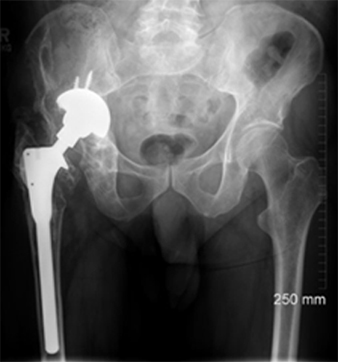

A middle-aged patient came to the clinic with severe pain and limited mobility in his left hip. Previously, he had undergone bilateral hip replacements that included modular necked femoral stems with ceramic-on-ceramic (CoC) bearings. However, the modular design led to corrosion between the titanium femoral stem and the cobalt-chromium neck, causing metal debris and an adverse tissue reaction in his left hip.

The challenge was in addressing the corrosion-related inflammation without exacerbating the damage to the surrounding bone, as the femoral stem was well fixed. Unlike cases with pseudotumors, the patient’s problem originated from metal debris due to the interaction of different alloys in the modular components.

Imaging studies confirmed the presence of metal debris and inflammation around the implant, particularly affecting the left hip. Despite the ceramic-on-ceramic bearing being intact, the corrosion at the modular junction between the neck and the stem was the main culprit. The diagnosis was an adverse reaction to metal debris, secondary to modular neck corrosion.

The surgery was successful, and at his six-week follow-up, the patient reported pain-free mobility and had resumed his daily activities. Imaging showed that the new primary stem had successfully integrated with the bone. At the two-year follow-up, the patient had a well-functioning hip, with no complications and clear evidence of bone growth around the implant, confirming the efficacy of the surgical approach.

This case represents ALTR with CoC. ALTR was characterized by tissue inflammation and extensive fluid accumulation around the ceramic implants. However, ALTR was not caused by the ceramic implant but by corrosion, which occurred between the titanium femoral stem and the cobalt-chromium neck.